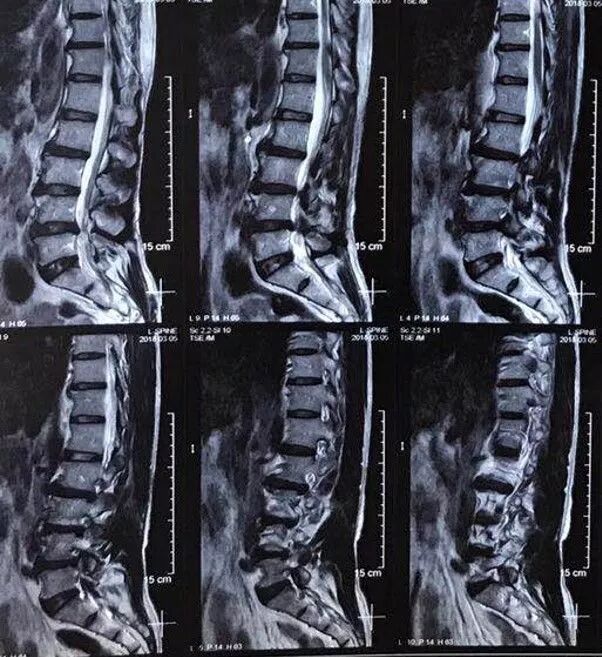

男性,59岁,半年前无诱因出现右半身麻木,伴右侧肢体乏力,右胸壁多汗,行走后右下肢抽痛明显,于当地医院就诊,查颈椎+胸椎+腰椎MRI示“颈髓脊髓空洞,腰4-5椎间盘突出”,对症治疗后症状无明显缓解。现为求进一步诊治,来西安交通大学第一附属医院,门诊以“脊髓空洞”收住入院。

影像学资料

1. Chiairi畸形并颈髓空洞

3. 腰4-5椎间盘突出